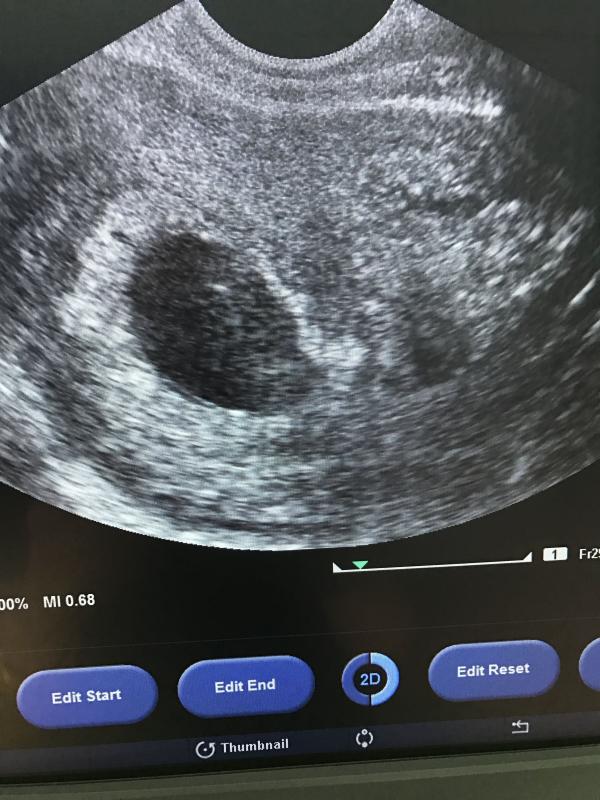

Сегодня мое утро началось с паники! Тяжелый день, обнаружила кровянистое выделение, в панике начала орать с туалета, позвала мужа, он вызвал скорую помощь! Забрали в БСНП, сдала мочу и узи...... и самое ужасное что я услышала "ребёнка не видно! Сделаем половое узи! Ребёнка нет в яйцеклетке!"...это как так?((((( я ходила с пустой яйцеклеткой 13 недель? Как такое вообще возможно? Пошли в платную клинику на Жибек Жолы-Наурызбай Батыра! Тоже сказали не видим ребёнка, все также сделали как и в больнице, подтвердили то что и в больнице... разве такое бывает?😢 реву, не могу((( так плохо.....не могу поверить!!!!!! Врачи сами в шоке, что яйцеклетка развивалась без эмбриона...

Да такое бывает называется анэмбриония, у меня так было , но мне сказали на 7 недели и сделали вакуумный аборт , очень жаль , держитесь все будет хорошо.